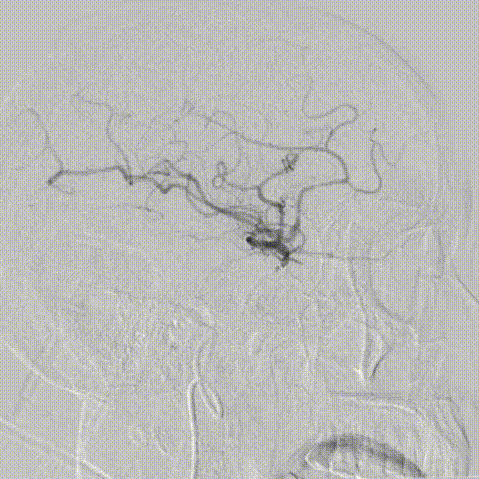

术中缓慢释放NeuroStellar®颅内支架头端后系统稳定,随后释放至支架尾端,造影提示支架打开满意,贴壁满意。

最后经6F中间导管正侧位造影留存影像后结束手术。